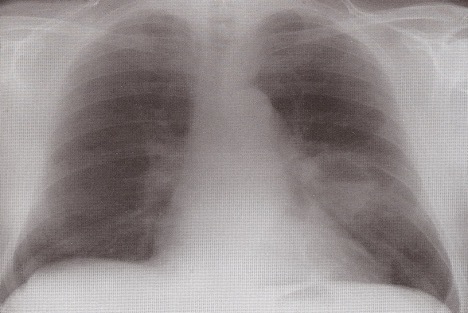

What features are seen on this CXR? What is the likely diagnosis?

Airspace fluffy shadowing

Pneumonia